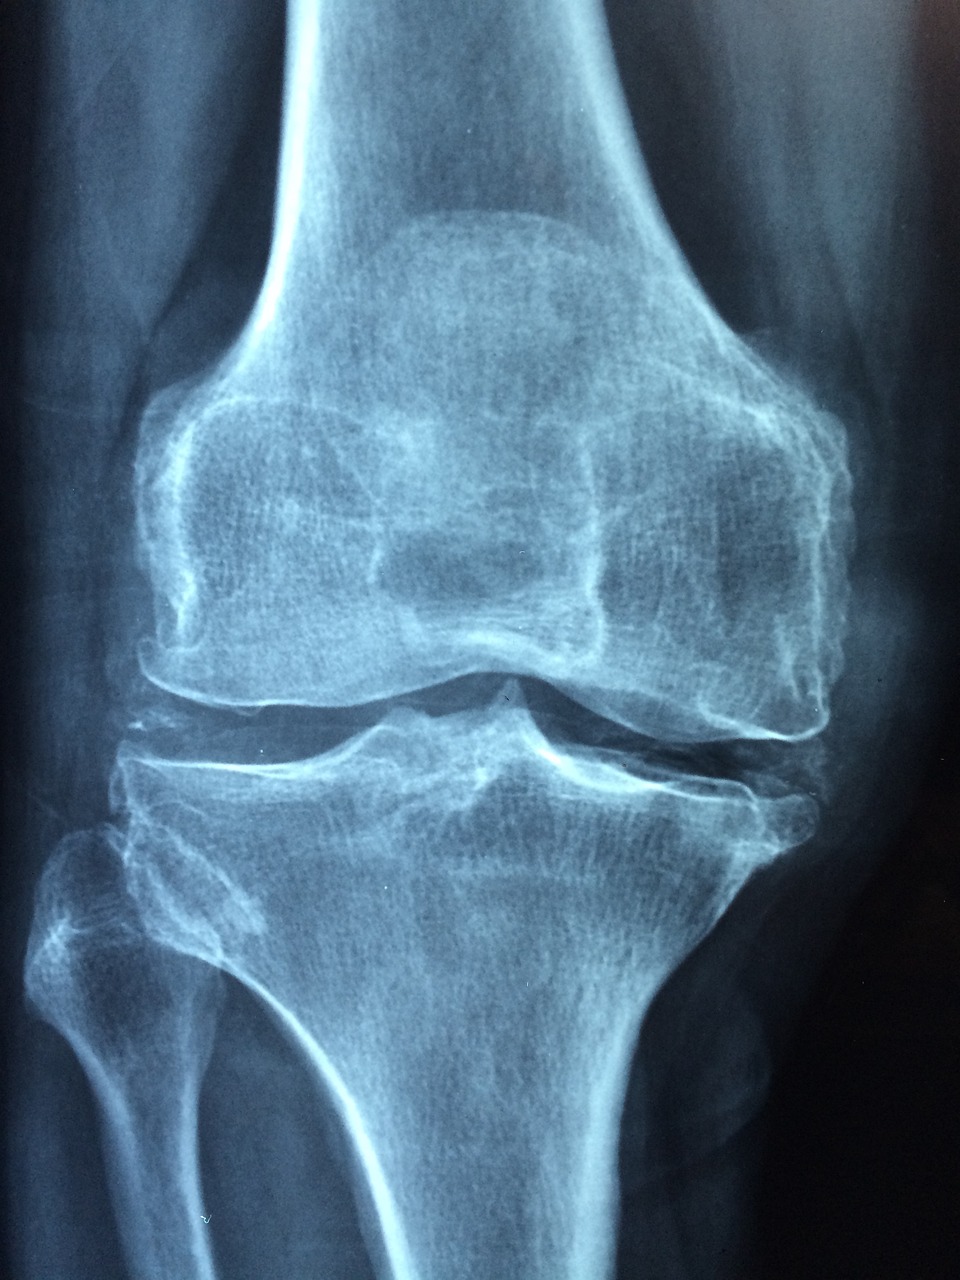

Total Knee Replacement

At VISDA Orthopaedics, we offer a superior alternative: Minimally Invasive Total Knee Replacement (MI-TKR).

This advanced technique, pioneered by Dr. Premkumar V, revolutionizes knee replacement surgery, providing patients with faster recovery times, reduced pain, and improved mobility.

Minimally Invasive TKR

Faster recovery, less pain with Minimally Invasive Knee Replacement. No muscle cutting is involved in our TKR procedure.